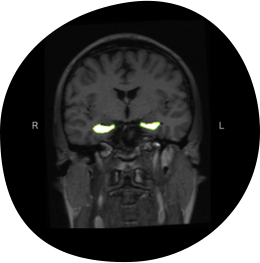

脳の萎縮は30代から少しずつ始まります。

特に認知機能の低下に大きく関わるのが、

記憶の中枢である「海馬」と呼ばれる部分の萎縮。

不健康な生活習慣やストレスの影響で、

海馬は簡単に萎縮してしまいます。

海馬の萎縮が進み、萎縮が脳全体に広がると、

アルツハイマー型認知症を発症することも。